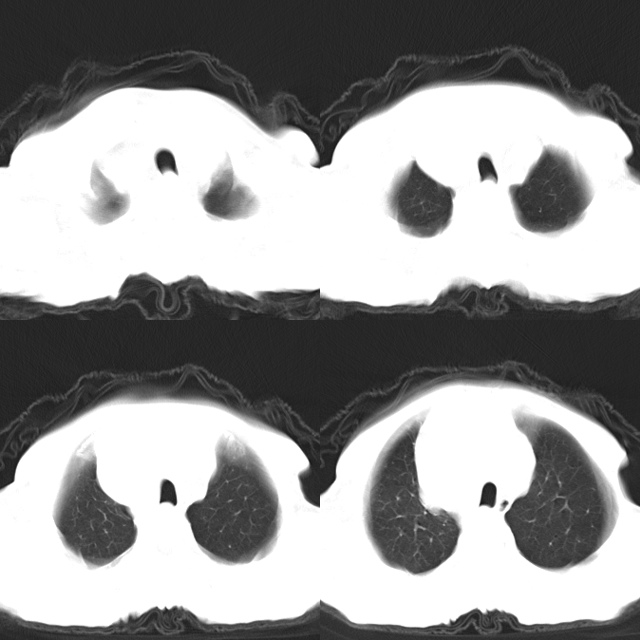

以下是引用心路寻觅在2010-4-17 18:35:00的发言:[br]纵膈多组淋巴结肿大呈“冰冻纵膈”,左肺上叶空洞伴其内结节密度影,考虑淋巴瘤伴左肺上叶曲霉菌感染。[br][br][本贴已被 心路寻觅 于 2010-4-17 18:36:23 修改过]

以下是引用zhangzhongshou在2010-4-17 19:32:00的发言:[br]一元论考虑左肺空洞型肺癌并纵隔淋巴结转移可能性大。